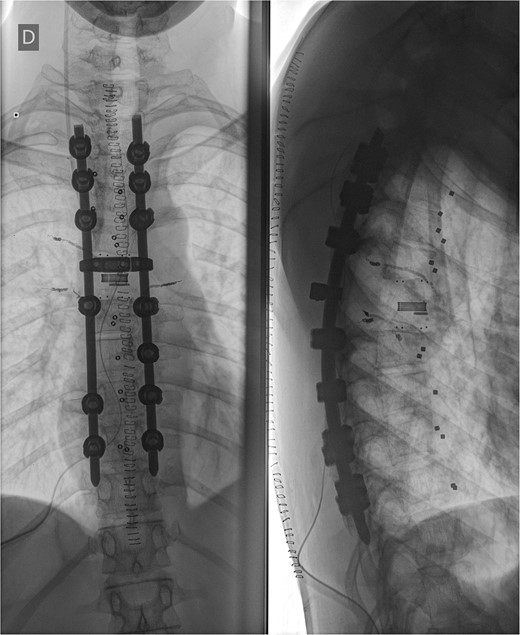

Postoperative X-ray imaging immediately after surgery; anteroposterior view (left) and lateral view (right).